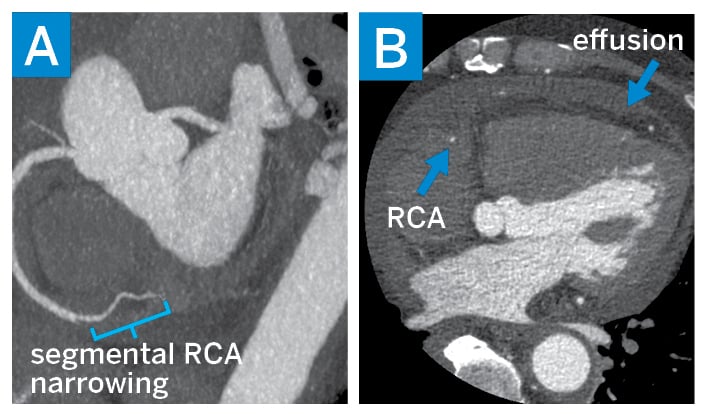

Laboratory workup showed leukocytosis with white blood cell count of 18,000 cell/mm3 and elevated C-reactive protein of 14 mg/dL. Cardiac magnetic resonance imaging (MRI) suggested the presence of an inflammatory process marked by pericardial thickening, myocardial edema, and diffuse late gadolinium enhancement. Cardiac computed tomography (CT) showed non-calcific single-vessel obstructive disease involving the right coronary artery (Fig. 2). A CT scan of the chest, abdomen, and pelvis showed diffuse soft-tissue thickening surrounding the aorta and superior mesenteric artery, as well as the adrenals and the perirenal and retroperitoneal spaces.

Figure 2

Figure 2: Cardiac CT: (A) a maximum-intensity projection view of the right coronary artery (RCA) showing a narrowing of the mid-RCA and (B) a short-axis view showing a stenotic RCA and pericardial effusion.